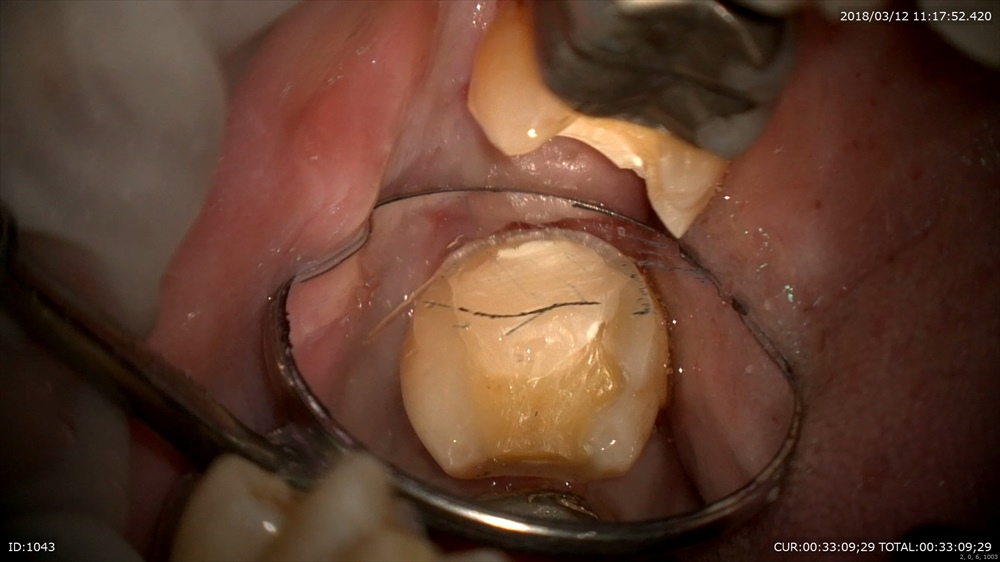

重症と診断した時点でラバーダム。無菌的治療は必須!

感染をとり

MTA

これで痛みが出なければ大丈夫!!